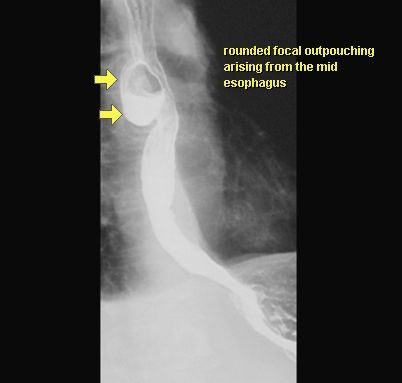

UCHYŁEK PRZEŁYKU

KONTRAST DO GOPP